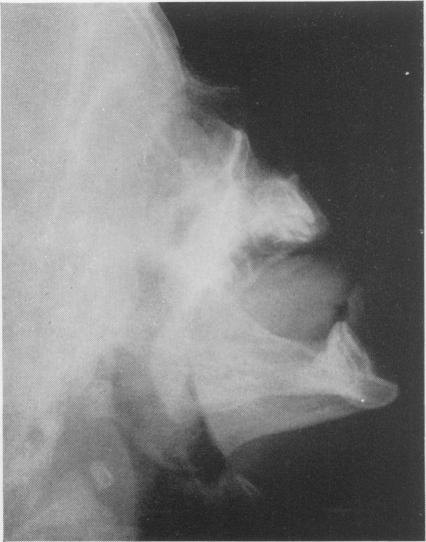

Anhidrotic ectodermal dysplasia presenting as a pyrexia of undertermined origin in the neonatal period.

Postgrad Med J. 1968 Feb;44(508):193-4. doi: 10.1136/pgmj.44.508.193.